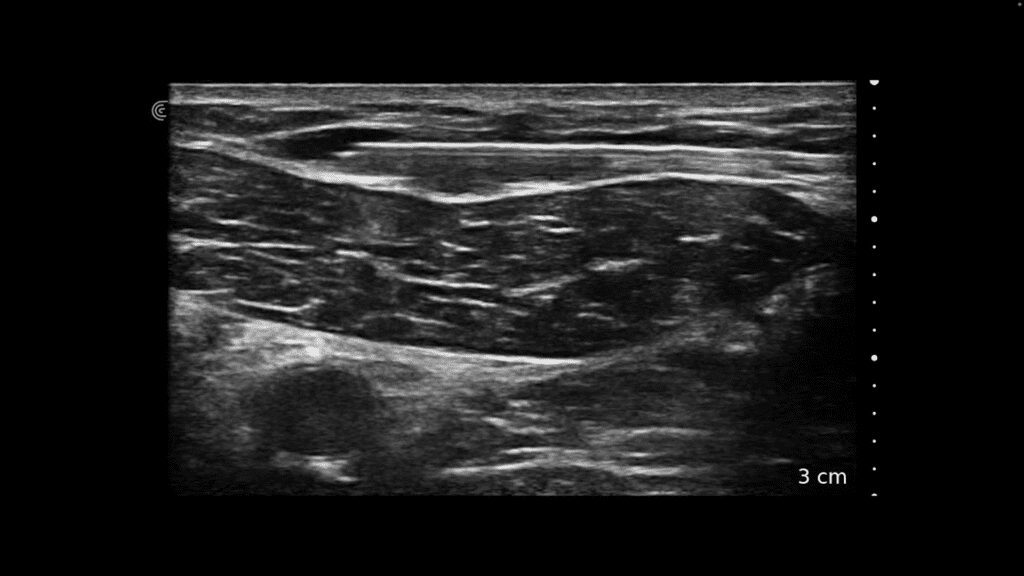

The size and respiratory variation of the inferior vena cava (IVC) can provide important information about the relative volume status of a patient. Find it just lateral to midline below the xiphoid process.